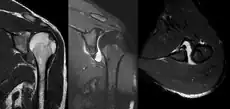

MRI of shoulder after dislocation with Hill-Sachs lesion and labral Bankart's lesion.

In young adults engaged in highly demanding activities shoulder surgery may be considered.[22] Arthroscopic surgery techniques may be used to repair the glenoidal labrum, capsular ligaments, biceps long head anchor or SLAP lesion or to tighten the shoulder capsule.[23]

Arthroscopic stabilization surgery has evolved from the Bankart repair, a time-honored surgical treatment for recurrent anterior instability of the shoulder.[24] However, the failure rate following Bankart repair has been shown to increase markedly in people with significant bone loss from the glenoid (socket).[25] In such cases, improved results have been reported with some form of bone augmentation of the glenoid such as the Latarjet operation.[26][27][28]